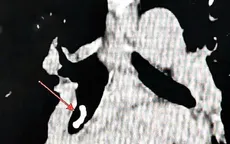

Nội soi lấy kim diệt tủy răng rơi vào tá tràng bé 8 tuổi

VTV.vn - Các bác sĩ Bệnh viện Trung ương Thái Nguyên vừa nội soi gắp dị vật là kim diệt tủy răng trong tá tràng bệnh nhi 8 tuổi.